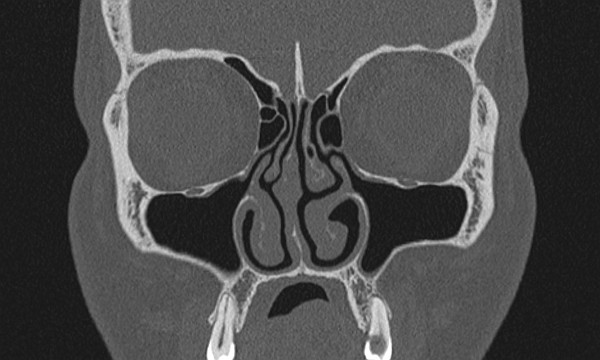

Coronal